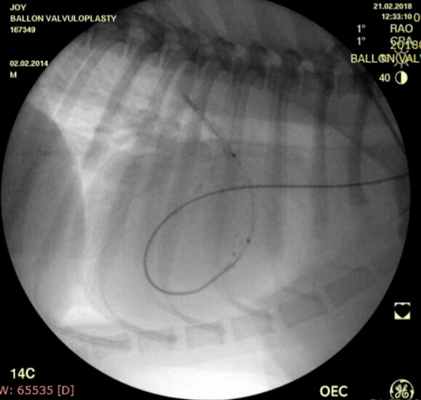

Проведено: баллонная вальвулопластика клапана легочной артерии (Тип А). Баллон Cordis maxi 40х20 мм. Инфляция до 5 атм. 10 попыток.

Показанием к оперативному лечению служит градиент систоличесокого давления на клапане легочной артерии свыше 50 мм рт.ст. При наличии дисплазии створок клапана — показана хирургическая коррекция порока, в остальных случаях возможно эндоваскулярное лечение. Операция выполняется в большинстве случаев под в/в анестезией, за исключением новорожденных, находящихся в критическом состоянии, у которых операция выполняется пол общим обезболиванием. Суть операции заключается в том, что после пункции бедренной вены в полость правого желудочка проводится и устанавливается катетер, далее проводник через клапан легочной артерии проводится в дистальные отделы легочной артерии. По проводнику в последующем проводится баллонный катетер и выполняется вальвулопластика. В настоящее время операция не сопровождается развитием летальных исходов и осложнений. Госпитальный период ограничен 3 днями.